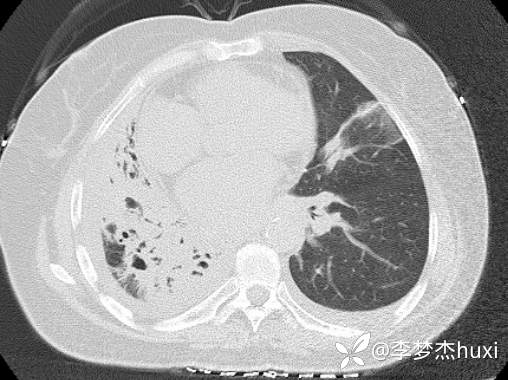

8.22治疗后的胸部CT: